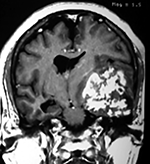

Cortes axiales en ponderación T1, cambios postquirúrgicos.

LA RMN muestra una lesión bien circunscrita frontal parasagital izquierda con edema perilesional, hiperintensa en T1 y T2, de contenido sólido y quístico, con poca captación del medio de contraste.

Se realizó craneotomía frontal para abordaje interhemisférico anterior.

Se realiza resección total de la lesión de contenido hemático oscuro-verdoso, consistente en un angioma cavernoso. La RMN postoperatoria se observa solo la brecha quirúrgica sin evidencia de lesión.

Figura 4:

Imágenes prequirúrgicas y postquirúrgicas de lesión multiloculada del caso 9.